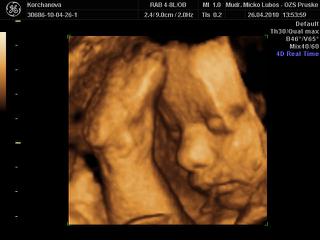

kocky ja som bola naposledy na 4D este pred vianocami co bolo v 5 mesiaci ktoho vie ako teraz vyzerame 😀 😀 😀 no hadam sa to uz o tyzden dozviem 😉

Ja som len zvedavá ked tam už teraz má málo miesta čo tam bude robiť ešte 10 týždňov,doky povedal že je to pod priemerom ale že ešte sa to dá 😒

ale aka zlatucka....to inak vyzera ako ked sme my videli v 20tt, to bolo take drobatko malinke....ja by som ho tiez chcela vidiet....ale uz si pockam....na osobne zoznamenie....